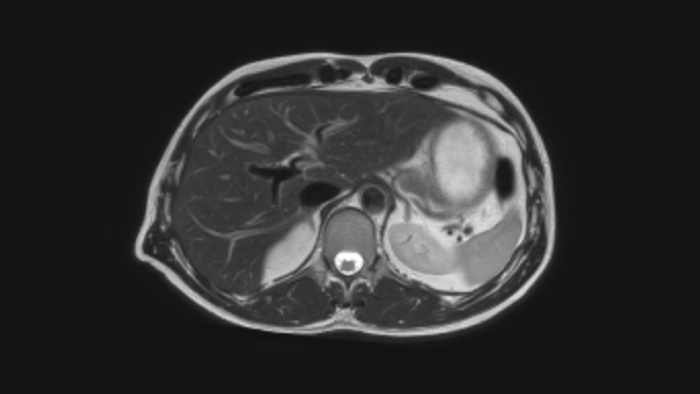

The new reality for your MR imaging

Now you can have it all with the Ingenia Ambition. It offers opportunities to improve your MR imaging at every level.

SmartSpeed SmartSpeed AI enables to decrease the scan time up to 65% with equal or better image quality

Speed & Comfort Provide up to 40% reduction in breath holds, with virtually equal image quality4.